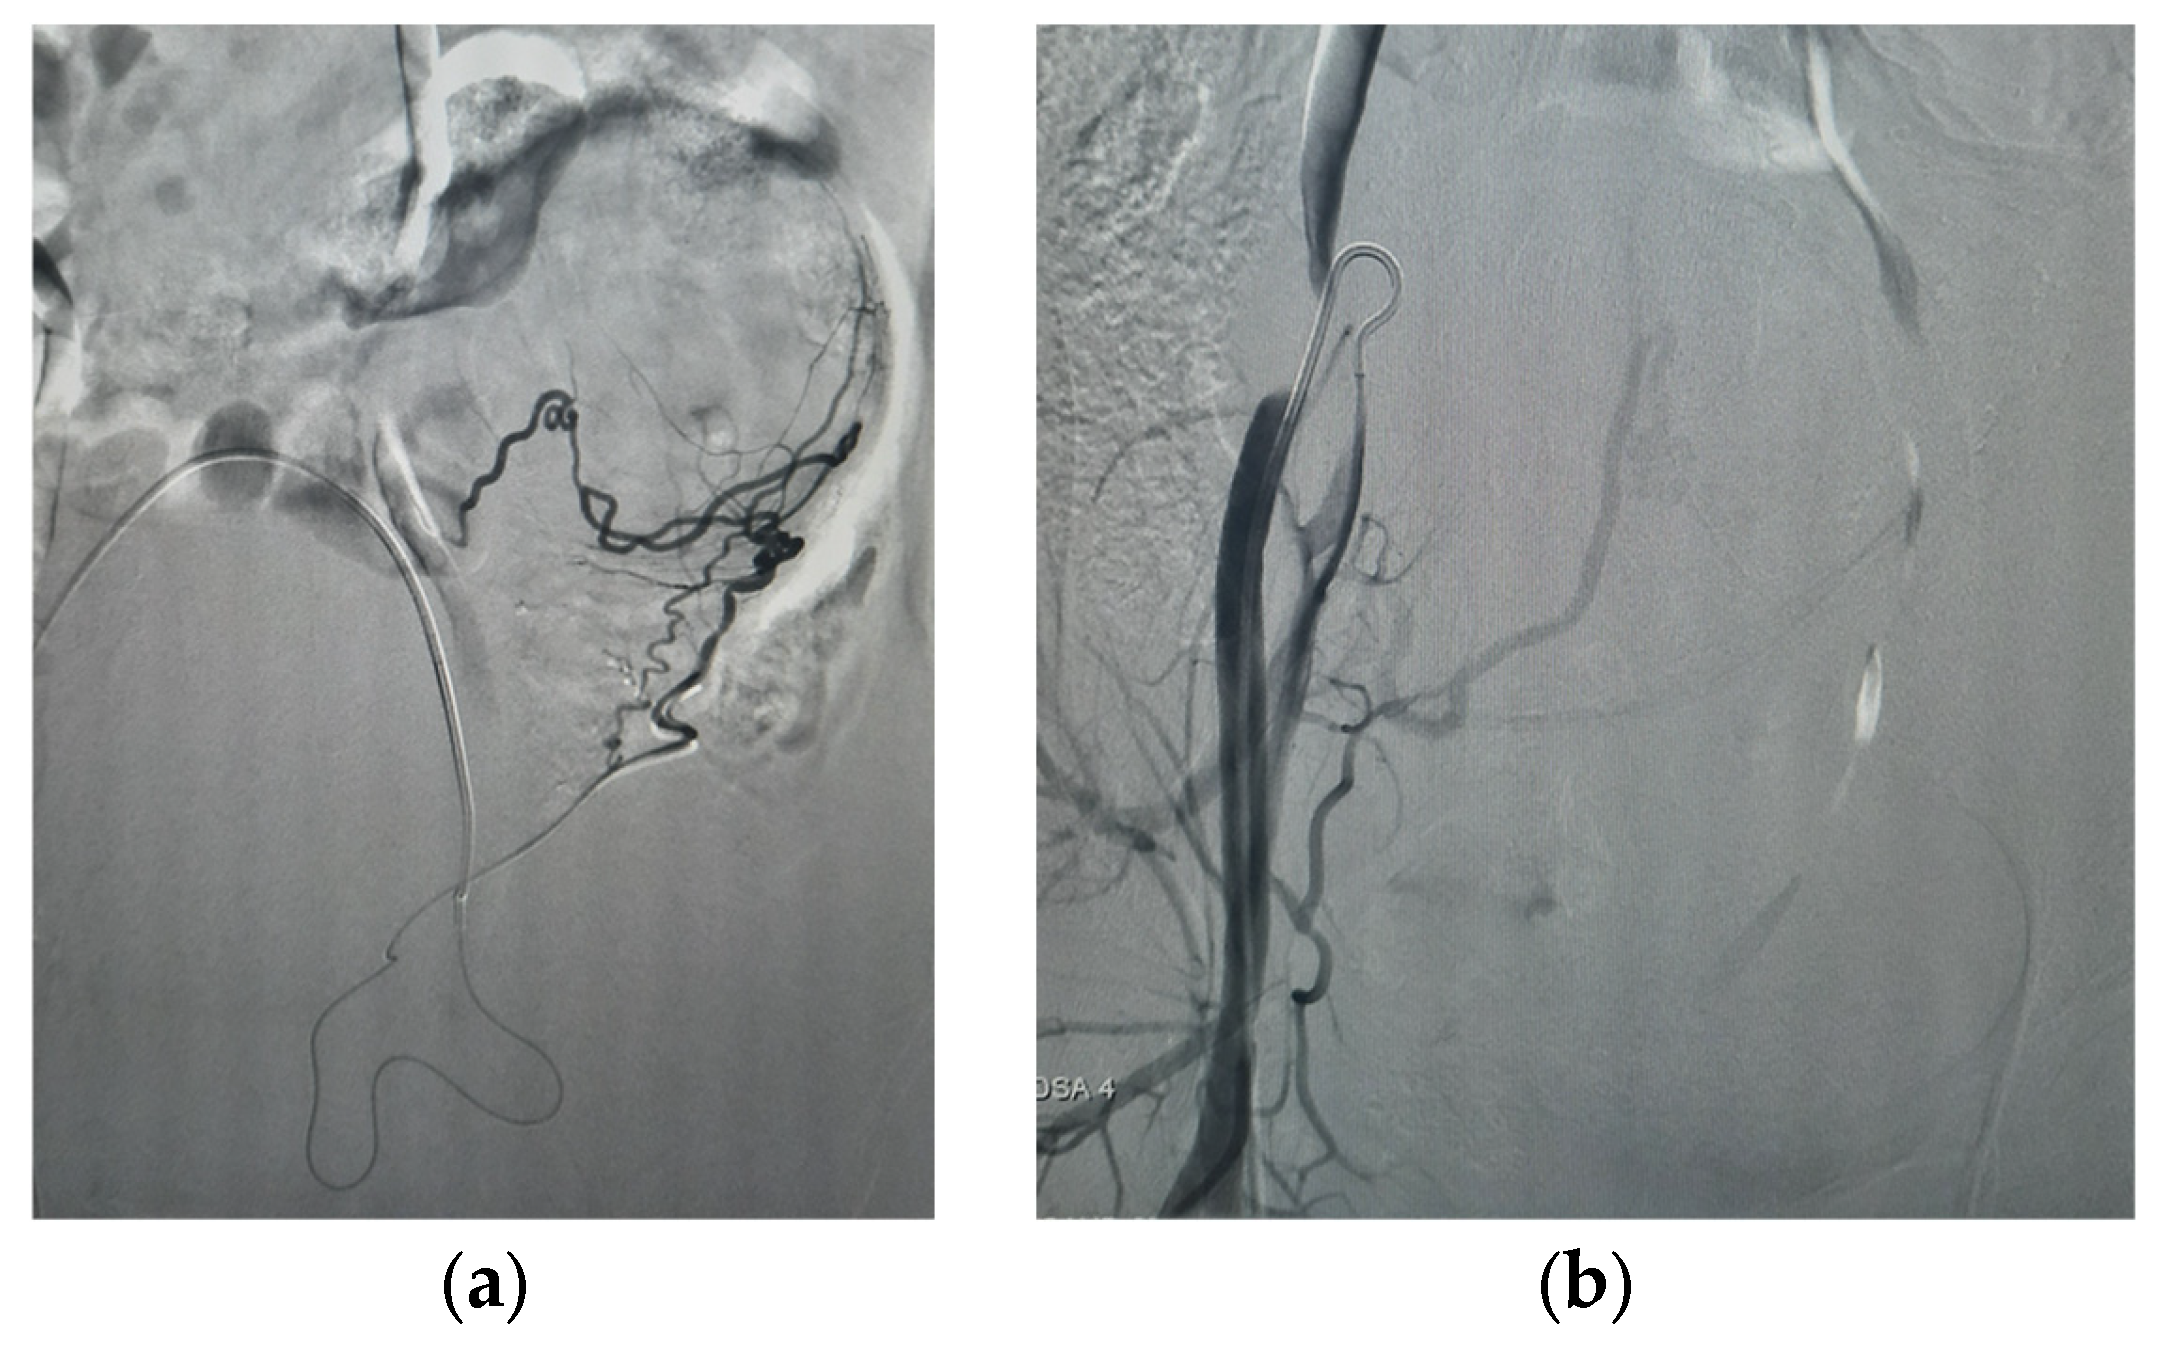

| 5 June 2025 (morning) | Selective bilateral PUAE performed using 800 μm particles + gelfoam; adequate devascularization achieved. |